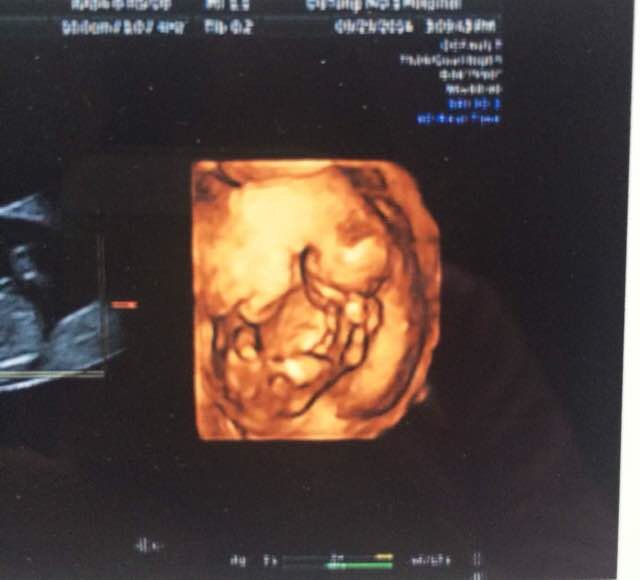

去做B超了,可以看出来是儿子姑娘么

怀孕后16周左右就可以做B超看出性别,B超单上面是看不出是男孩还是女孩,只有在做B超的过程当中才可以看出来